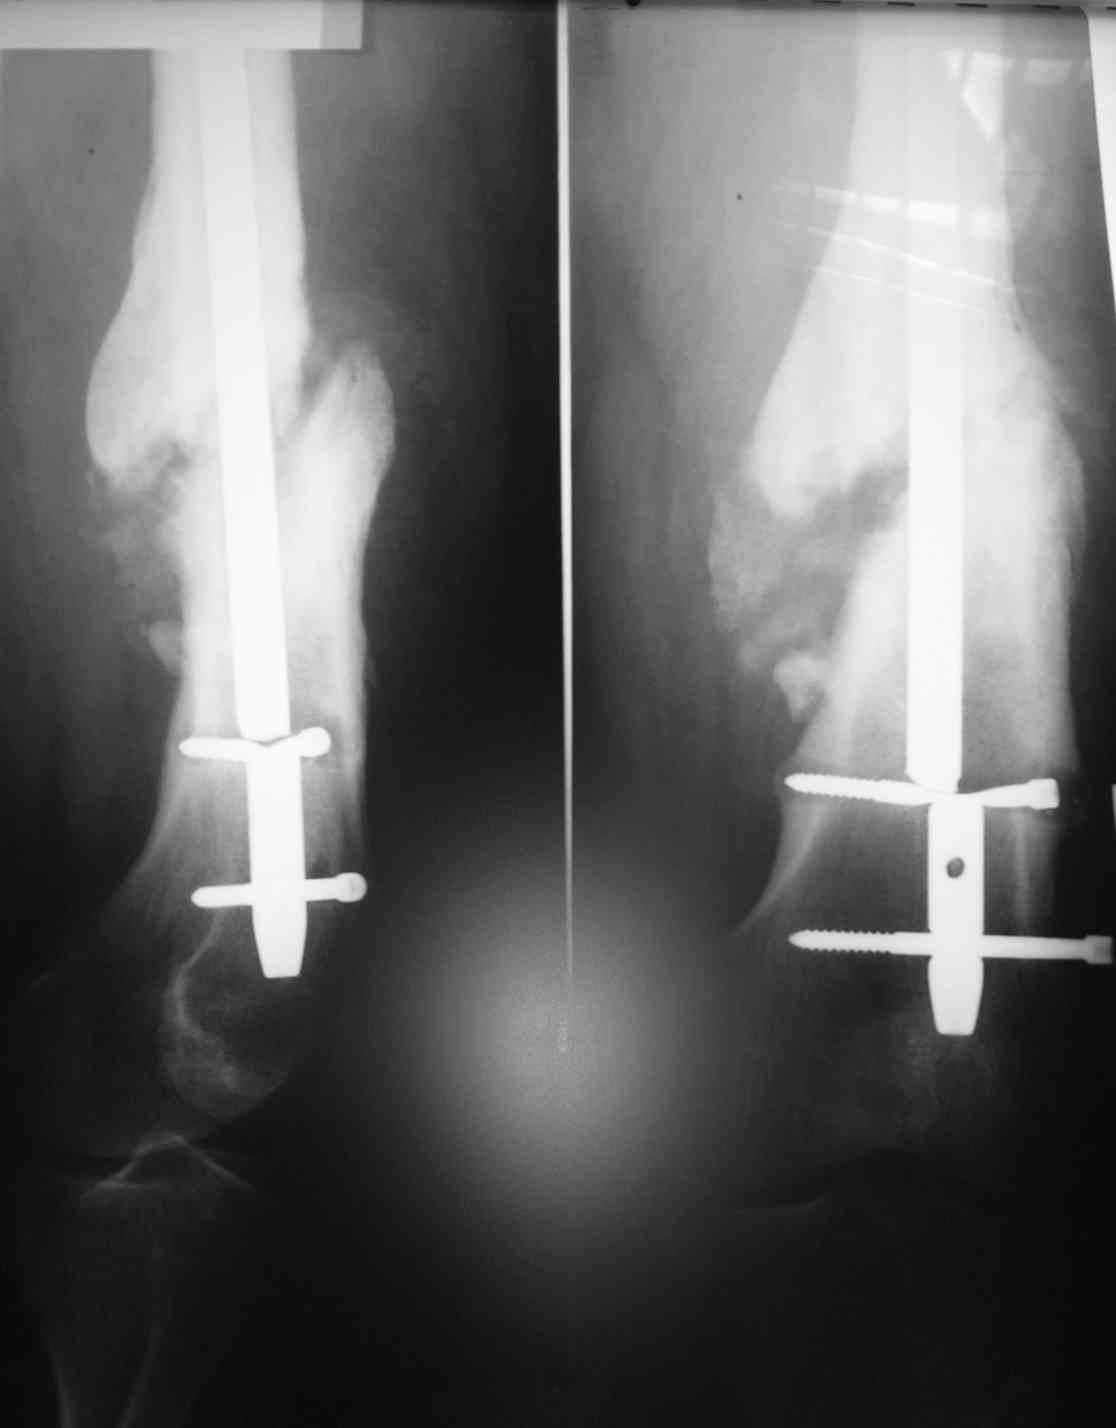

Обратился мужчина, 120 кг, из анамнеза: 1.5 года назад была проведена операция установка антеграднего стержня в связи с переломом в дистальном отделе бедренной кости.

Спустя 1.5 года - несросшийся перелом кости и перелом стержня.

недавно обратился к травматологу из-за возникшей боли. Посоветуйте, как наиболее доступно и наименее травматично удалить эту конструкцию? Тактика дальнейшего оперативноголечения?

Мы планируем после удаления старой конструкции, установку ретроградного бедренного стержня с рассверливанием и первичной динамизацией.